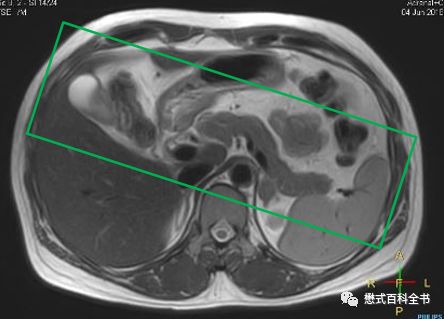

有的时候,如果要诊断胆囊结石或者胆管结石,相对难度不大。明显的结石,经常在常规的横轴位T2WI或者冠状位T2WI上即可显示。难度大的在于胆总管下段的占位或者不确定的梗阻。

图28:横轴位显示明显的胆囊结石